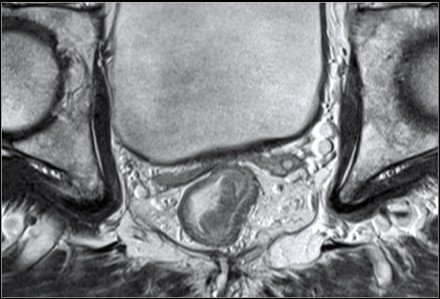

- Đánh giá di căn hạch vùng trên cộng hưởng từ:

Theo AJCC hạch vùng bao gồm: quanh trực tràng, mạc treo sigma, dưới mạc treo, bên cùng, trước cùng, chậu trong, Gerota, chậu ngoài, trực tràng trên, trực tràng giữa, trực tràng dưới.

Một hạch nghi ngờ là hạch di căn trên CHT khi thuộc một trong ba  trường hợp sau:

- Trường hợp thứ nhất, hạch có kích thước <5mm kèm với ba đặc điểm ác tính (hạch bờ không đều, tín hiệu hạch không đồng nhất, hạch hình tròn).

- Trường hợp thứ hai, hạch có kích thước 5-9mm kèm hai trong ba đặc điểm ác tính (hạch bờ không đều, tín hiệu hạch không đồng nhất, hạch hình tròn).

- Trường hợp thứ ba, hạch có kích thước  >9mm luôn luôn xem là hạch nghi ngờ.

Hình 9. Hai hạch nghi ngờ di căn ở phía trong cân mạc treo trực tràng